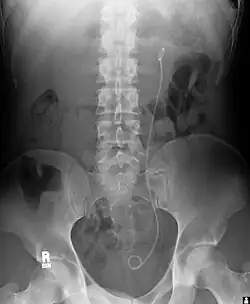

Example of a ureteral stent used to alleviate hydronephrosis of the kidney

Ureteral stents are used to ensure the patency of a ureter, which may be compromised, for example, by a kidney stone. This method is sometimes used as a temporary measure to prevent damage to a kidney caused by a kidney stone until a procedure to remove the stone can be performed.

An ureteral stent it is typically inserted using a cystoscope, and one or both ends of the stent may be coiled to prevent movement. Ureteral stents are used for various purposes, such as temporary measures to prevent damage to a blocked kidney until a stone removal procedure can be performed, providing drainage for compressed ureters caused by tumors, and preventing spasms and collapse of the ureter after trauma during procedures like stone removal. The thread attached to some stents may cause irritation but allows for easy removal by pulling gently.

Stents without threads require cystoscopy for removal. Recent developments have introduced magnetic retrieval systems that eliminate the need for invasive procedures like cystoscopy when removing the stent. The use of magnets enables simple extraction without anesthesia and can be done by primary care physicians or nurses rather than urologists. This method has shown high success rates across different patient groups including adults, children, and kidney transplant patients while reducing costs associated with operating room procedures.